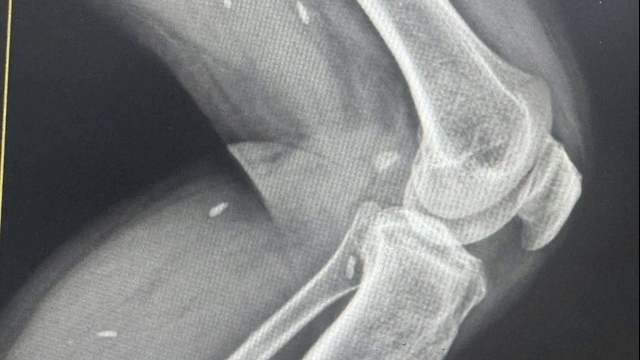

Ông Nguyễn Vũ Sâm là bệnh nhân đang nằm điều trị tại Trung tâm ung bướu – Y học hạt nhân, Bệnh viện đa khoa tỉnh Vĩnh Phúc. Đêm ngày 28/10/2022, ông Sâm đã chứng kiến người bệnh Khổng Văn Sơn (quê ở Xuân Hòa – Lập Thạch) điều trị cùng phòng bệnh, bị cơn đau dữ dội lúc 02 giờ 05 phút và sau đó đã được Bệnh viện chẩn đoán là vỡ khối u gan do khối u lớn và phát hiện muộn.